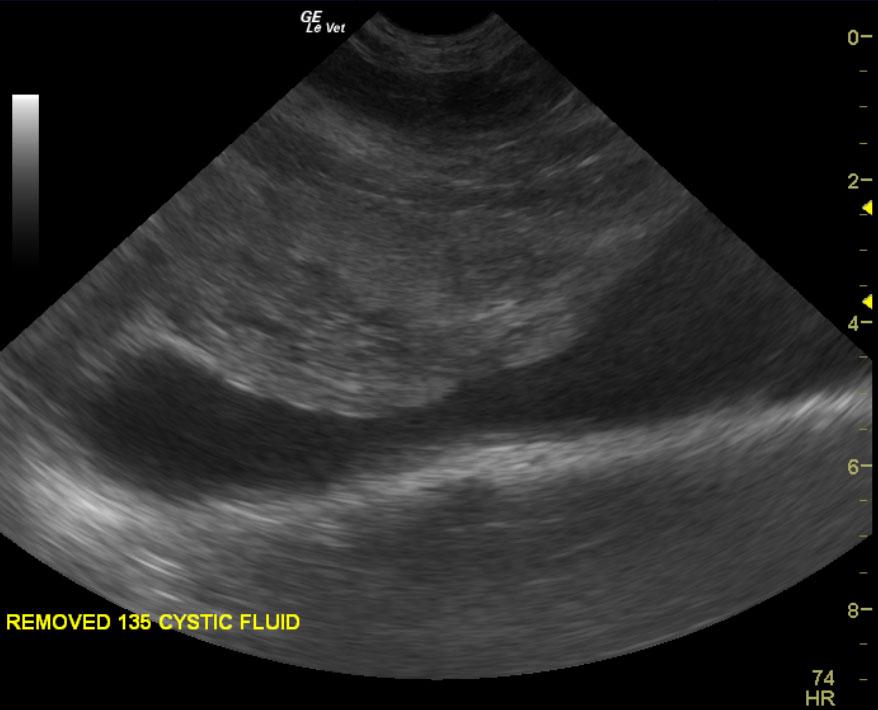

A ten year old intact male labrador retriever was presented with an enlarged prostate and painful rear end. Serum biochemistry and CBC were within normal limits. The urine specific gravity was 1.022 with mild pyuria.